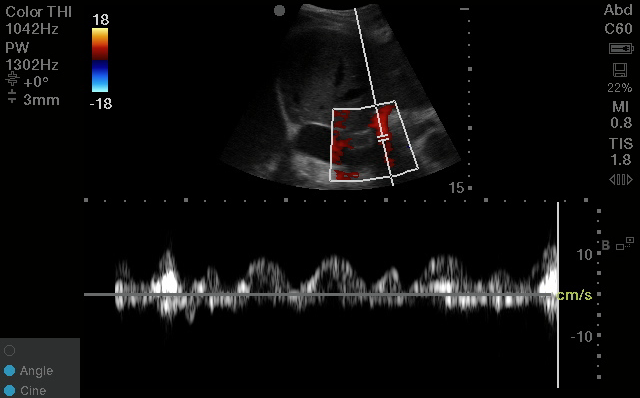

A quick #VEXUS thread 🧡-

3 reasons why the portal vein is the most useful single venous doppler waveform πŸ₯‡

(if you're only going to do ONE site to look for venous congestion, this is probably the most useful one!) 1. It's easy to obtain

Unlike the intra-renal veins, which can be elusive even to the most experienced scanners, the portal vein is usually easily identifiable.

From a right-sided coronal plane in the mid-axillary line, with your liver and kidney in view, the move is typically to fan or slide your probe in the anterior-posterior plane.

You should see a nice vertically-aligned segment of the portal vein pop into view; easily recognized by its bright hyperechoic borders and hepatopetal blood flow (which will look RED on colour doppler).